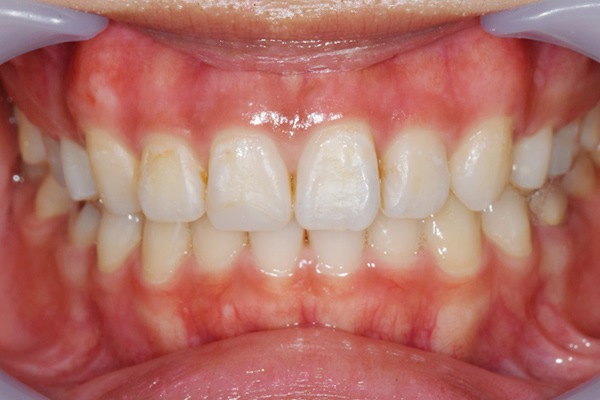

症例2

治療前

治療後

| 年齢・性別 | 39歳・男性 |

|---|---|

| 主訴 | 歯ぐきの色が気になる |

| 治療内容 | 上下顎ガムピーリング |

| 治療費 | 11,000円(2022年10月現在) |

| 治療期間 | 1回30分 |

| リスク・副作用 | 一時的に歯ぐきが白くなりますが、10日程度でピンク色の歯ぐきになります。施術後はやけどをしたようなヒリヒリ感が出ることもあります。 |

| 担当者所見 | 定期的に繰り返し施術することで更にピンク色に近づけることも出来ます。 |